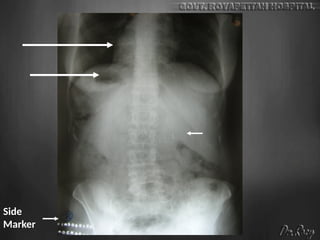

Abdomen

checklist

• Exposure

• Rotation

• Diaphragm + above and below

• Liver Spleen Kidney Psoas shadow

• Pelvis

• Calcification

• Abnormal bowel gas pattern / extraluminal air

• Soft tissue mass

• Visualized bones

liver

RK

LK

UB

Psoas line

Side

Marker

•NORMAL PLAIN X-RAY OF

•Normally the stomach and colon

contain gas that can show here,

particularly if the patient is not well

prepared

•Normally the small intestine

contains no gas (or a very minimal

amount). Small bowel gas shadow

may normally show in one or two

very small loops at most